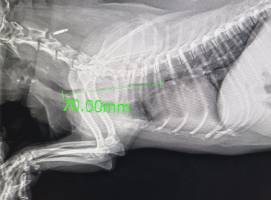

Kardiologia weterynaryjna to specjalistyczna dziedzina zajmująca się diagnostyką i leczeniem chorób serca.